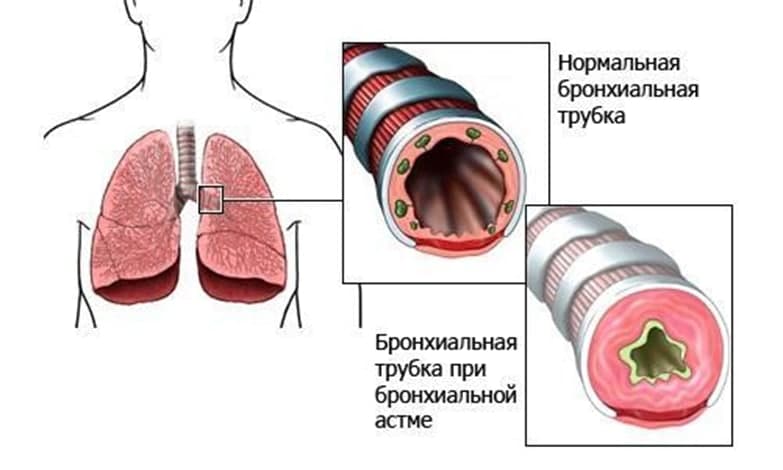

Здоровье дыхательной системы: бронхи и легкие